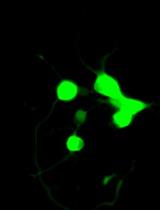

• This protocol provides detailed instructions on the synthesis of fluorescently labeled emulsion microgels using mucoadhesive whey protein isolate, allowing the replication of this process.

• The protocol describes in detail how to prepare samples for confocal microscopy.

2. Preparation of samples for confocal microscopy: The microgels are prepared for analysis by confocal microscopy, which helps to visualize their structure and distribution.